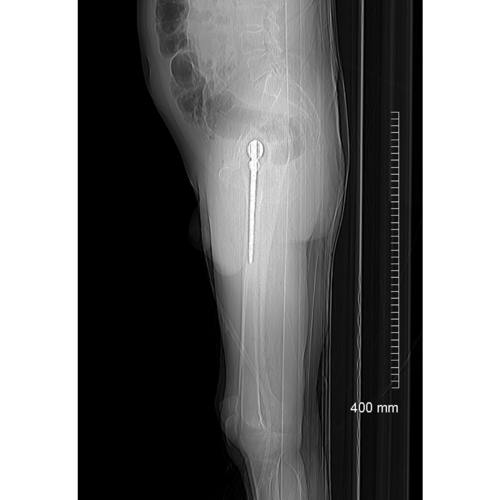

Scannograms show the pre-operative situation before the second stage of this patients procedure